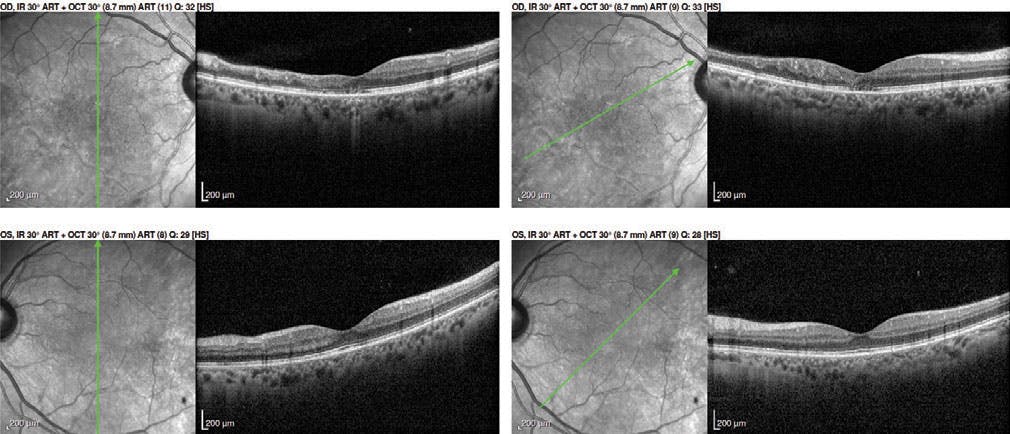

Fundoscopy showed a temporal subretinal hemorrhage accompanied by discrete vitreous hemorrhage in the vicinity, as well as Berlin macular edema (Figure 1). No tears or signs of retinal detachment were noted. A CT scan of the orbits detected the presence of a metallic foreign body adjacent to the lateral wall with no signs of retrobulbar hemorrhage or damage to the globe or extraocular muscles (Figure 2). The surgeons who observed the foreign body opted for conservative course, and thus, it was not removed from the orbital cavity at this time.

At the 2-week follow-up, the patient’s VA had recovered to 20/20 OS. OCT of his left eye showed a disorder of the retinal pigment epithelium cells in the damaged area, with no signs of macular edema (Figures 3 and 4). Retinography revealed a resorbing lower temporal vitreous hemorrhage and a retinal hemorrhage that had already reabsorbed.